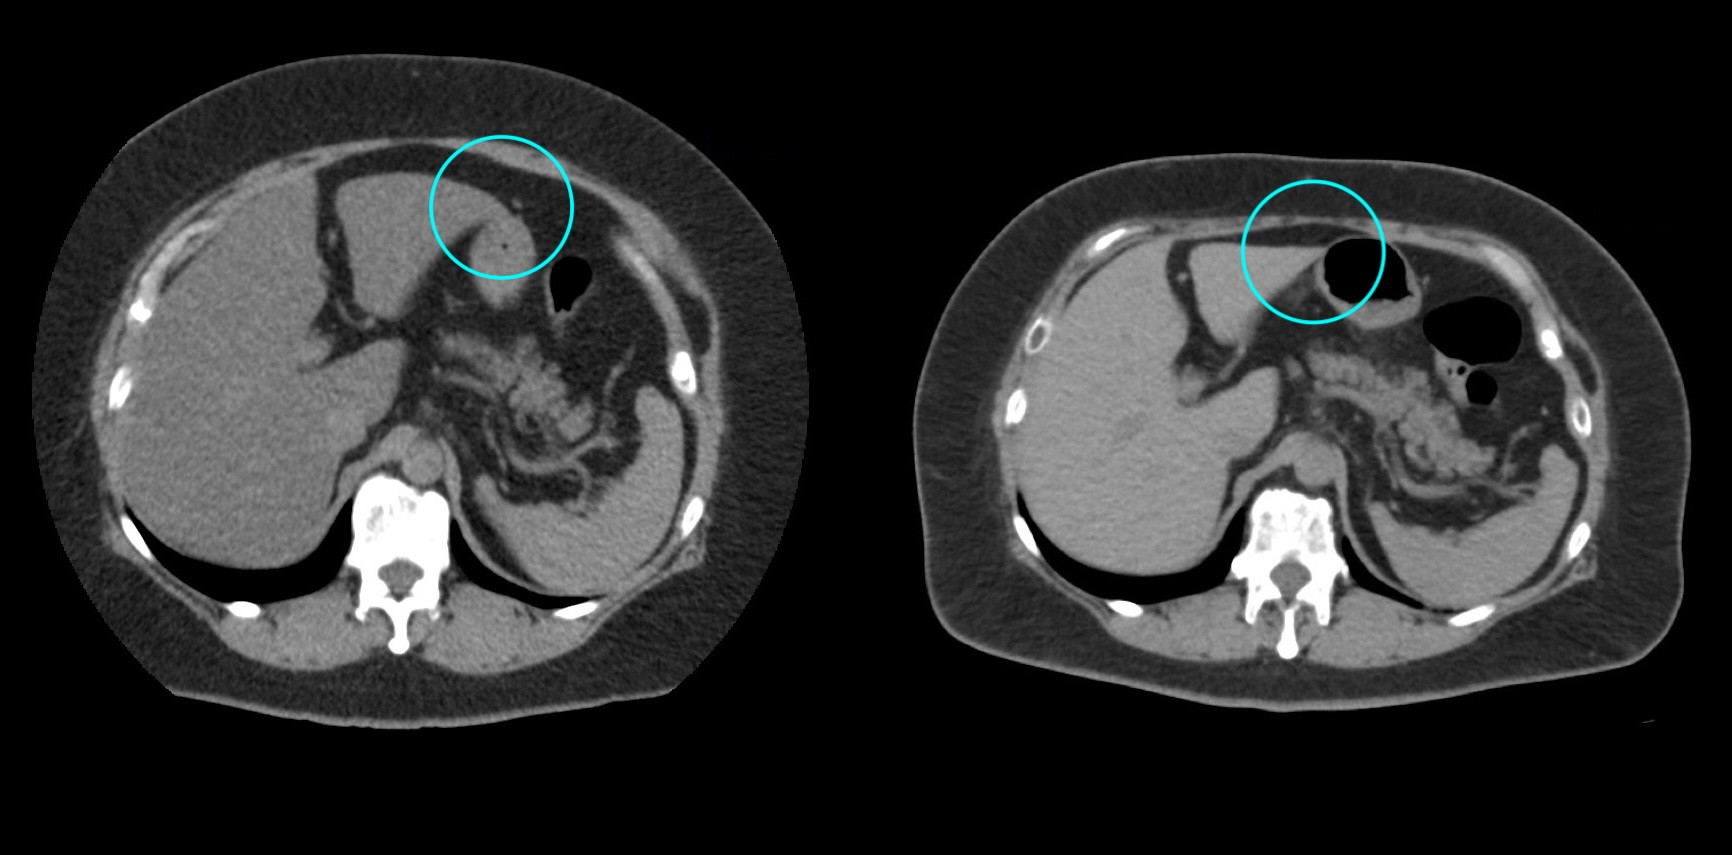

①

50代・女性(ご本人のご厚意で画像提供)

治療内容:チルゼパチド7.5mgの週1回自己注射による脂肪減少と脂肪肝改善

治療期間: 12ヶ月(52週)((用量は2.5mgから開始し最大で15mg。減量効果が得られる必要用量には個人差があります。))

費用:自由診療の場合は9900円(税込)×52(週)=514800円

想定されるリスク・副作用:下記に副作用を記載

※医療広告ガイドラインに準拠して表記

2:脂肪肝の改善

沈着した脂肪の減少による肝臓の平均CT値の増加(20から50へ)(脾臓の平均CT値は両者とも50)

bluntness of the liver edgeの改善(青色部分)